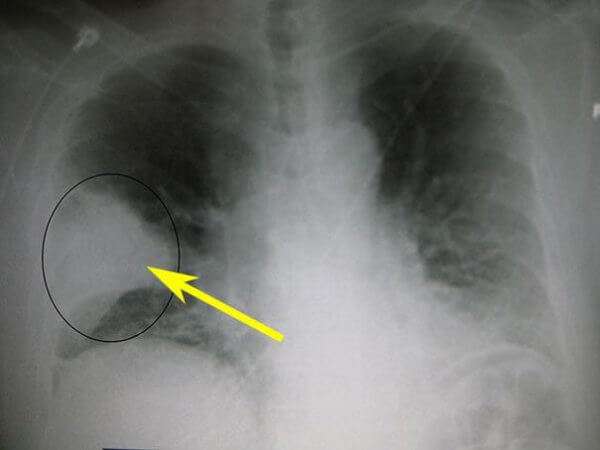

Как отличить бронхит от пневмонии по результатам рентгеновского снимка

классический вариант бронхита на рентген-снимке

пневмония на рентген-снимке: видно почти полное затемнение нижней доли

Несмотря на некоторые различия пневмонии и бронхита, нередко клиника бывает размытой. В такой ситуации для установления верного диагноза необходимо сделать флюорографию или рентгенографию – это наиболее достоверный способ диагностики. По результатам рентгенограммы лечащий врач сможет легко распознать болезнь. Худшие опасения подтвердятся, если на снимке будут отчётливые затемнения.

| Рентген | Усиление лёгочного рисунка | Очаговые затемнения |